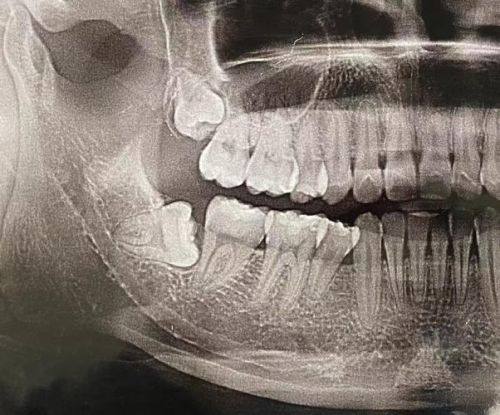

16. 口腔全景片:100 - 300元

2. 种植牙:引进韩国登腾、奥齿泰、法国安卓健、瑞典诺贝尔、瑞士士卓曼等多种种植体系统,适合不同缺牙人士的种植需求。

2. 章蓉:拥有近二十年口腔临床经验,在口腔种植修复,牙齿美白及牙齿残根残冠的保留修复等方面有较深的造诣,擅长微创种植牙、微创即刻种植、微痛种植牙、全口/半口牙颌种植、牙贴面。